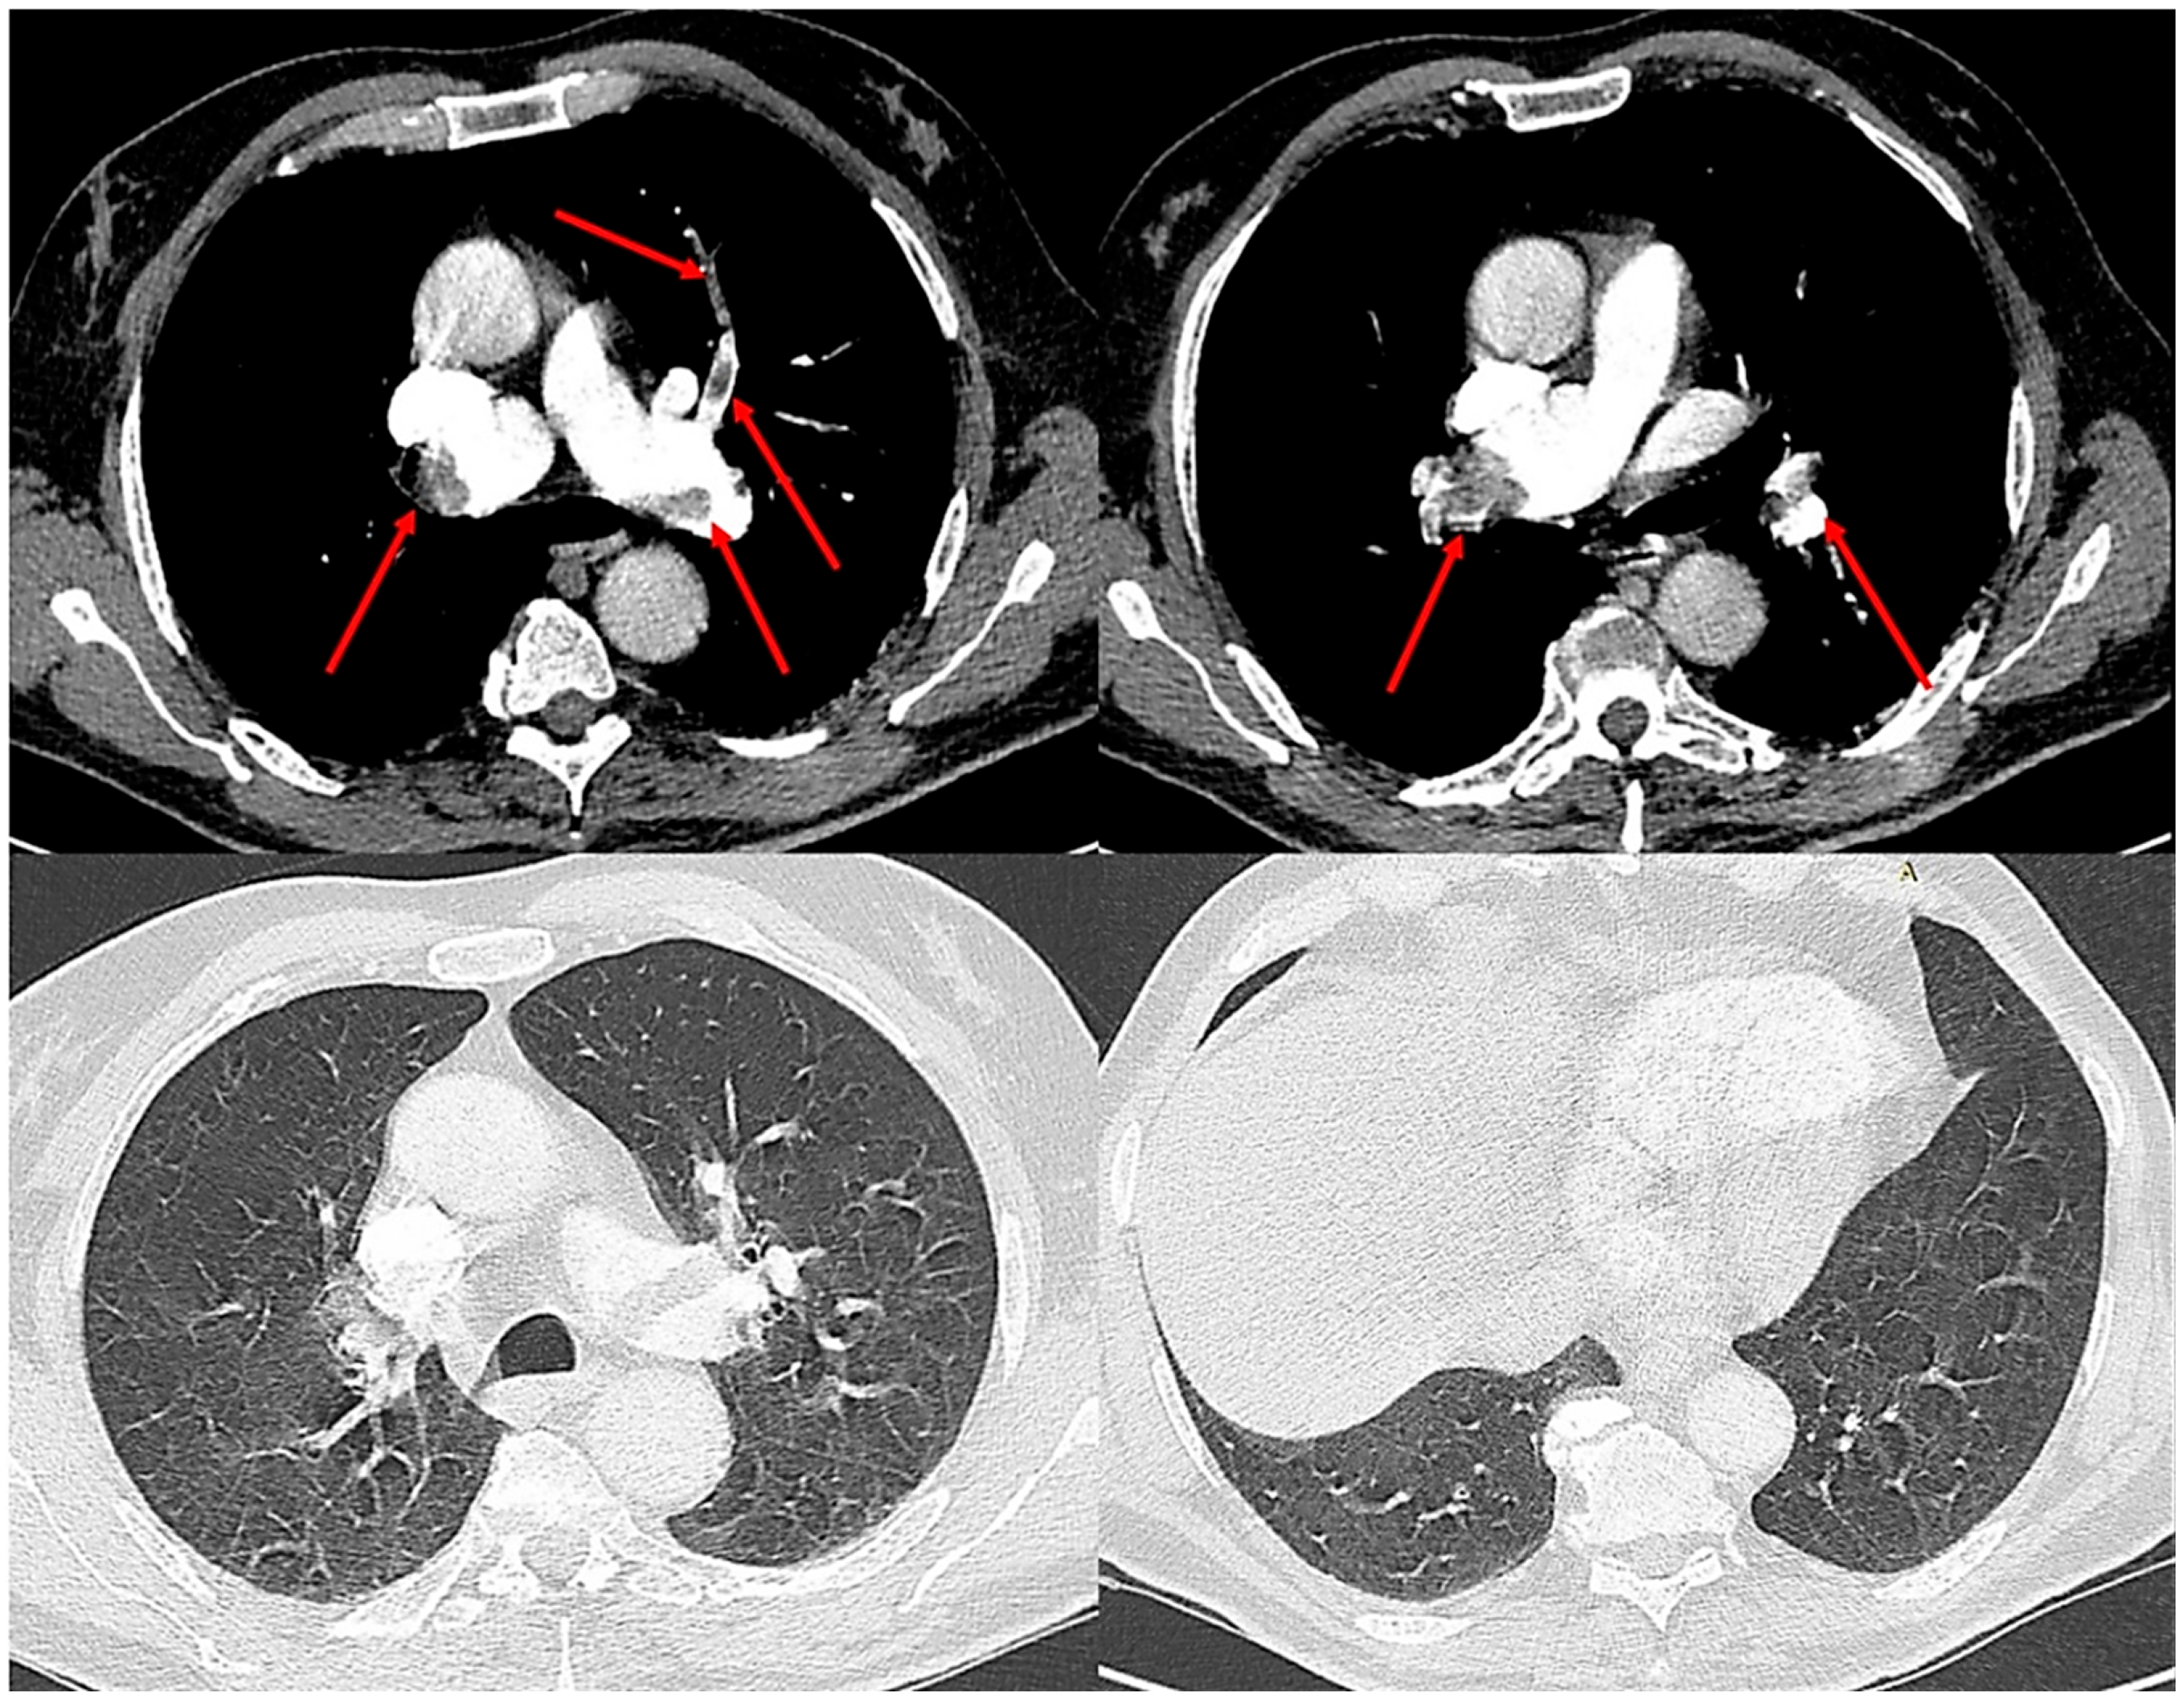

A supine chest radiograph demonstrated normal cardiac size and clear lung fields, without focal consolidation, pleural effusion, or pneumothorax (Figure 1).

No abnormalities were identified that could explain the profound hypoxemia. Electrocardiography revealed sinus tachycardia with an S1Q3T3 pattern and incomplete right bundle-branch block, consistent with right-heart strain.

Figure 1. Supine chest radiograph obtained in the emergency department showing no focal consolidation, pleural effusion, or pneumothorax. The lung fields and costophrenic angles are clear, and cardiac size is within normal limits. No radiographic abnormalities are identified to explain the patient’s profound respiratory distress.